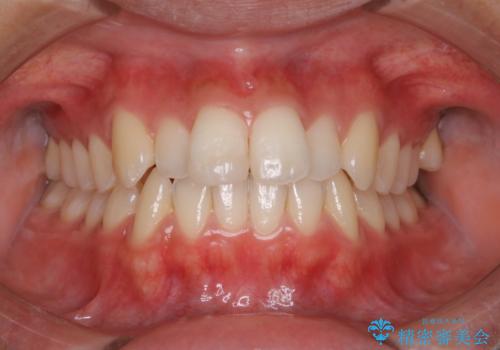

部分矯正中のクリーニング